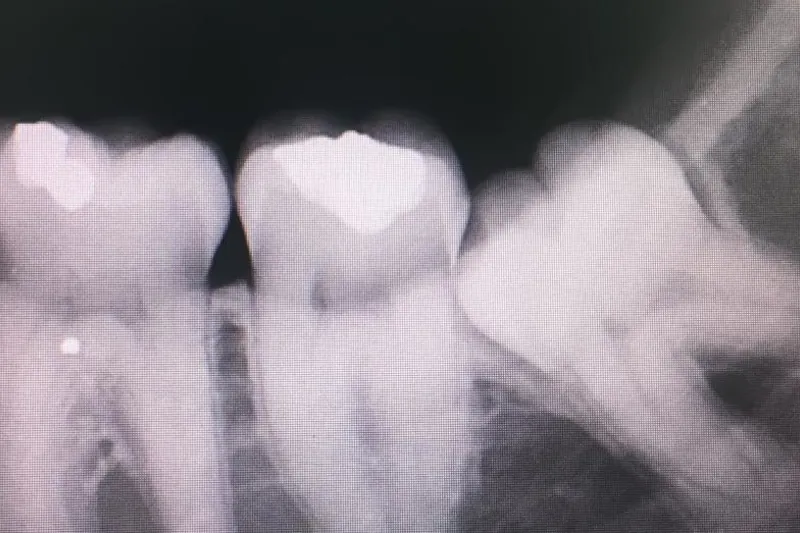

Skal retinerede tredjemolarer fjernes, inden de giver symptomer, eller skal man vente med behandling, til der opstår tilstande som fx caries, pericoronitis eller periapikal sygdom?

Patienter, der fik fjernet tænder på grund af symptomer, havde færre postoperative gener som smerte, hævelse og trismus i de første dage efter indgrebet end patienter, der fik foretaget indgrebet på profylaktisk indikation. Til gengæld var risikoen for længevarende gener større i denne gruppe. Et særligt problem udgjorde iatrogene nerveskader på n. alveolaris inferior. Sådanne komplikationer forekom fx hos 0,9 % af de 12-16-årige, hos 4,2 % af de 26-35-årige og hos mere end 5,6 % af patienterne over 35 år.

På baggrund af disse resultater konkluderer forfatterne, at det kan være fornuftigt at fjerne retinerede tredjemolarer, inden patienten fylder 25, da risikoen for kompliceret forløb stiger med stigende alder.